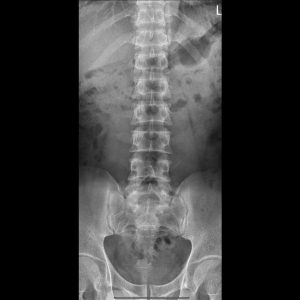

L-spine AP view

L LAT.Seq2.Ser1.Img1

L-spine Lateral view

L-spine Oblique view(RPO)

L-spine Oblique view(LPO)​

L-spine Lat Ext.

L-spine Lat. Flex.